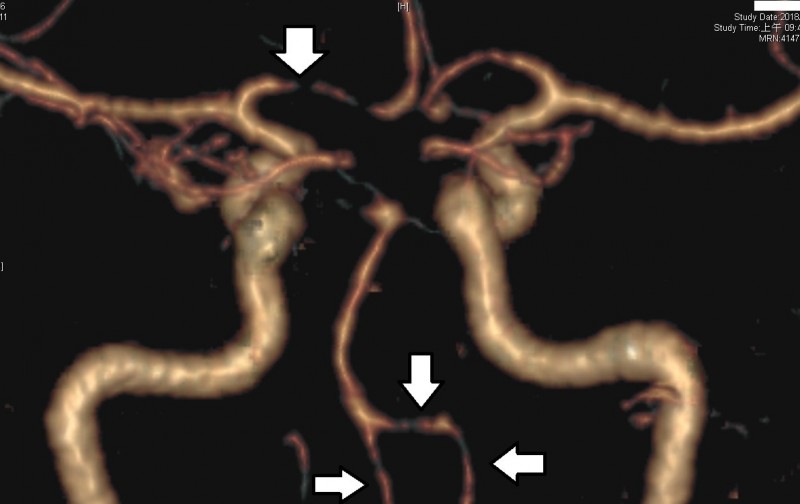

可逆性腦血管收縮症候群 華人健康網

經常頭痛 小心 可逆性腦血管收縮症候群 龔晉賢診所健康園地 痞客邦